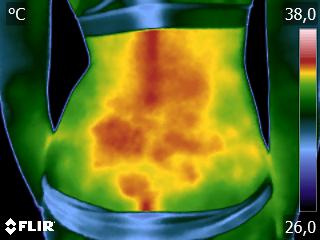

Como no caso da sequência de termogramas abaixo de uma paciente do sexo feminino, 42 anos, sem comorbidade e que apresentou dor em joelhos após treino de musculação. Foi realizado uma Análise Termofuncional e detectado alterações térmicas condizentes com o relato de dor.

Estas informações foram a oportunidade para convencer a paciente a realizar uma ressonância magnética para determinar o grau de comprometimento tecidual. Pois sem isso, após a melhora da dor, a liberação de carga e até a carga terapêutica ficariam limitadas.

Já com este conhecimento foi possível determinar um tratamento que abarcasse as áreas de dor e as áreas de comprometimento tecidual que apresentam inflamação, até a paciente retornar com o resultado da ressonância.

Isso adianta e muito a reabilitação, pois oferece informação que a olho nu não seria possível.